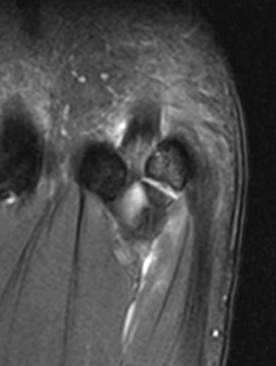

Edema on T2 MRI indicates likely acute fracture